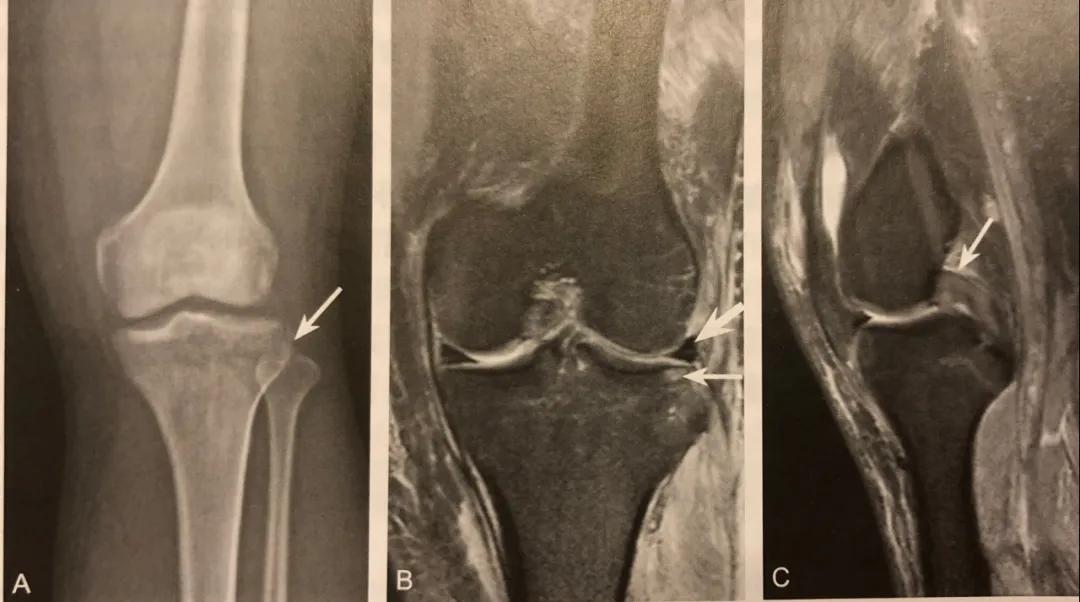

弓形征

A. Ⅹ 线前后位片,腓骨茎突撕脱性骨折,呈弓形征,骨折线为横形,撕脱碎骨片向外上方移位,碎骨片长轴水平走行

B. CT 骨三维重建,清晰显示弓形征、撕脱骨折碎骨片移位方向

C. PDWI SPAIR冠状位示,腓骨小头撕脱骨折(粗箭头)股二头肌腱和外侧副韧带附着,外侧副韧带信号增高,提示损伤(细箭头)

弓形征在膝关节 X 线前后位片或 CT、MRI 冠状位显示,表现为近端腓骨小头或腓骨茎突撕脱性骨折,骨折线呈横形状或斜形,撕脱碎骨片大小不一,碎骨片多向外上方移位,碎骨片长轴水平走行。

MRI 显示腓骨头髓腔或碎骨片水肿,T1WI 低信号,T2WI 高信号,T2WI STIR 高信号。

阅片要点:

1. 腓骨小头撕脱性骨折的直接征象,弓形复合体和后外侧角损伤的间接征象;

2. 在膝关节X线前后位或 CT、MRI 冠状位观察,表现为近端腓骨小头或腓骨茎突撕脱性骨折,碎骨片呈弓形;

3. X 线片或 CT 观察到弓形征后,须行 MRI 检查,观察弓形复合体及后外侧角的完整性;

4. 少数后外侧角损伤合并腓总神经及胭动静脉损伤。